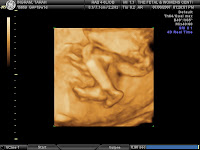

Today we had our 19 week ultrasound and everything looks great! The little guy could not hold still for more than 3 seconds. He is already SUPER active! Most of the pictures we got are 3-D, so I just picked out a few to put on here. Call me an over-excited-first time mom...but I could probably put 100 on here so it was hard for me to narrow it down! We can hardly wait until December!!

This is the only non-3-D picture that we got. I know that the 3-D ones are a little more "creepy" than these normal ones.